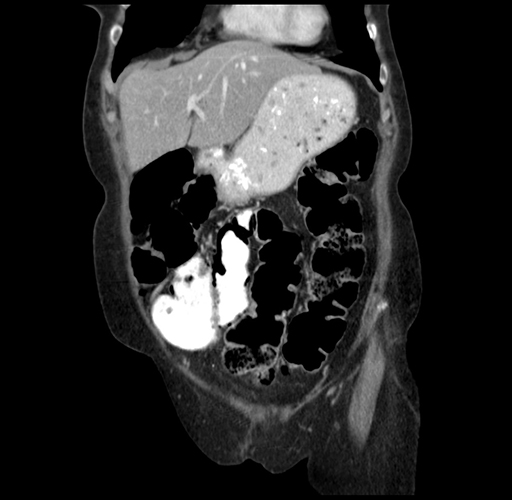

Pre-Chemo: Axial Venous

Axial Venous